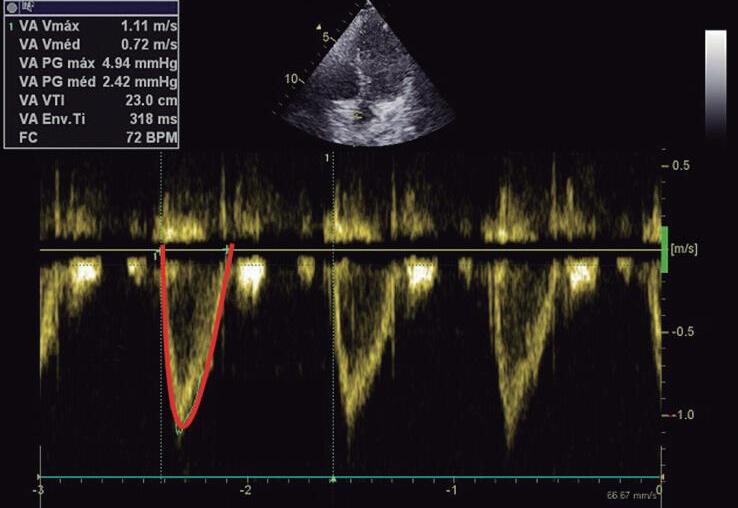

Fig. 1-10. Plano apical 5 câmaras demonstrando: (a) imagem em 2D e (b) com Doppler colorido. (c) Tracejando o fluxo obtido pelo Doppler do fluxo de via de saída do VE (VSVE) é possível obtermos a velocidade de tempo integral (VTI). A VTI da VSVE associada à área da VSVE (mensurada no plano paraesternal eixo longo do VE) e a frequência cardíaca possibilita o cálculo do débito cardíaco do VE pela fórmula: {VTI × área da VSVE em cm} × fC (ver detalhamento no Capítulo 3). AD: átrio direito; AE: átrio esquerdo; VD: ventrículo direito; VE: ventrículo esquerdo; s: septo interventricular; Ao: aorta.